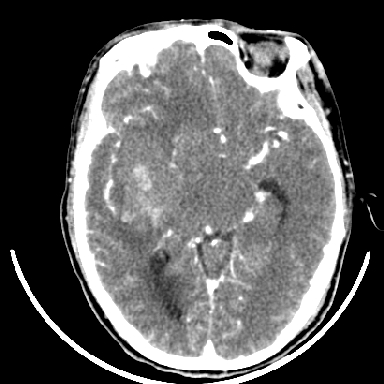

标题: CT6056:脑出血(血管畸形?) [打印本页]

标题: CT6056:脑出血(血管畸形?)

m 40突发头痛左侧偏瘫3小时

考虑高血压性脑出血,依据:

1是高血压性脑出血的好发部位,形态呈肾形,是高血压性脑出血的常见形状

2增强时占位效应加重了,考虑出血还没有停止

3病灶周围水肿不是太厉害,一般肿瘤出血水肿多非常明显

4病灶周围的‘软组织’影没有明显的强化

5至于脑血管畸形引起的出血,暂时没有看到明显的畸形血管影,也不太支持

支持右侧基底节脑出血

右侧基底节区脑出血.

支持右侧基底节区(主要为外囊区)原发性脑出血。

另附部分资料:“血液溢出血管外形成血肿,其内含有大量血红蛋白、血浆白蛋白,球蛋白,因这些蛋白对x线的吸收系数高于脑质,故ct呈现高密度阴影,ct值达40~90h,最初高密度灶呈非均匀一致性,中心密度更高,新鲜出血灶边缘不清。基底节区血肿多为“肾”型,内侧凹陷,外侧膨隆,因外侧裂阻力较小,故向外凸,其它部位血肿多呈尖圆形或不规则形”

术中抽出40ml陈旧血液,血肿底部似见一条索血管影